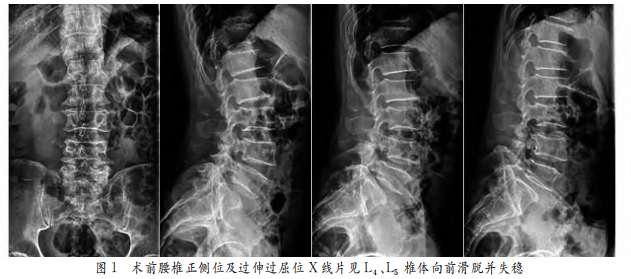

45°(+)加强试验(+),右下肢直腿抬高试验(-)。入院后腰椎正侧位及过伸过屈位X线片示腰椎L4、L5椎体向前滑脱、腰椎不稳(见图1);腰椎MRI+增强扫描示L5S1水平椎管内左侧见类圆形病灶,病灶内为略长T1长T2信号,边缘见环状低信号,相应水平椎管狭窄,病灶边缘明显强化,内见斑点状不均匀强化(见图2);腰椎CT示L5S1水平椎管内左侧黄韧带肥厚、占位性病变(见图3)。初步诊断为“腰椎滑脱症、腰椎椎管内占位(黄韧带囊肿?)”。完善相关术前检验、检查,排除手术禁忌后行腰椎后路椎间盘切除椎管减压滑脱复位植骨融合内固定+椎管内肿物切除术,术中见L5S1椎间盘水平椎管内左侧黄韧带内侧一囊性肿物,囊壁包绕、粘连左侧S1神经根,连同黄韧带一起完整分离剥除囊性肿物,约2.0cm×1.2cm×0.8cm(见图4),剖开囊壁见灰黑色浑浊液体。病理结果:退变的纤维、软骨组织,纤维母细胞增生及小血管增生,局灶黏液性变,未见肿瘤细胞,符合囊肿病变(见图5)。术后随访1年,患者左下肢疼痛、麻木症状明显改善,左下肢踝背伸、足母背伸、跖屈肌力基本恢复正常(见图6)。